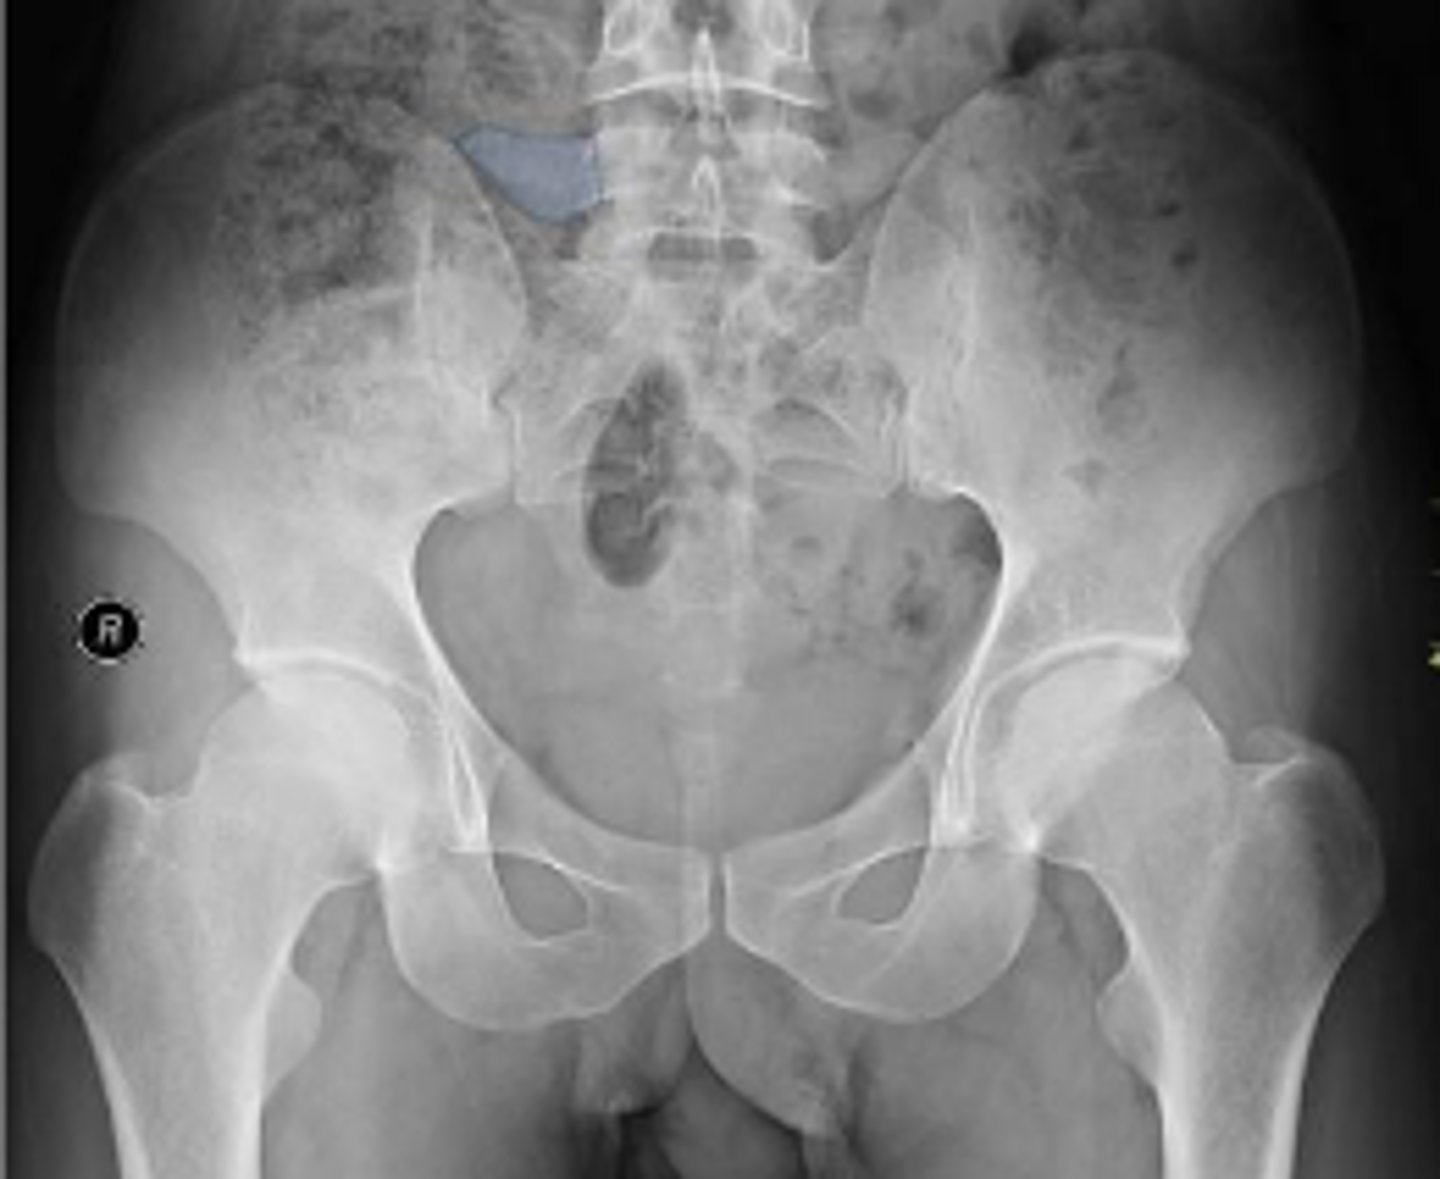

AP pelvis or bilateral hips

What is the name of the radiographic view?

Sigmoid colon

What is outlined?

L4/L5 IVD space

Which IVD space is indicated by the arrows?

Right L5 transverse process

Coccyx

Left superior pubic ramus

What are the arrows pointing to?

Left inferior pubic ramus

AIIS

Soft tissue outline

Right ischial tuberosity

Proximal lateral cortical outline of the diaphysis of the right femur

Right S3 superior border of the sacral foramen

L3/L4 IVD space

What IVD space is indicated by the arrows?

Left and right posterior inferior iliac spine

Posterior rim of the left acetabulum